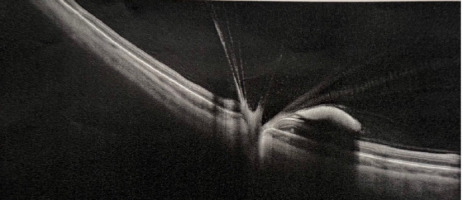

Figure 2

A, B. Ultrasound B-scan examination of the left eye on the day of admission, vitreous hemorrage is indicated by red arrows